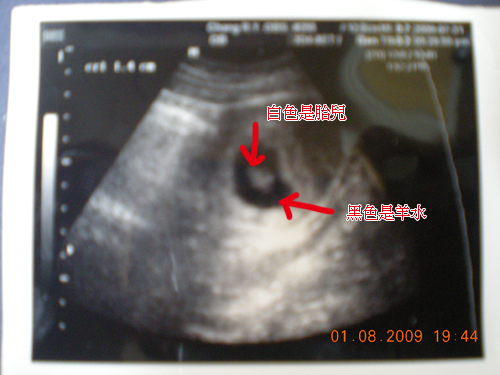

第七週了~BABY有心跳了~我聽醫生弄給我看心跳~因為聲音很好玩~所以我不爭氣的笑了!!

可是有生命在體內跳動呢~好感動~雖然小小的~白色部份就是BABY了~才1.4公分唷^^ 好可愛喔~